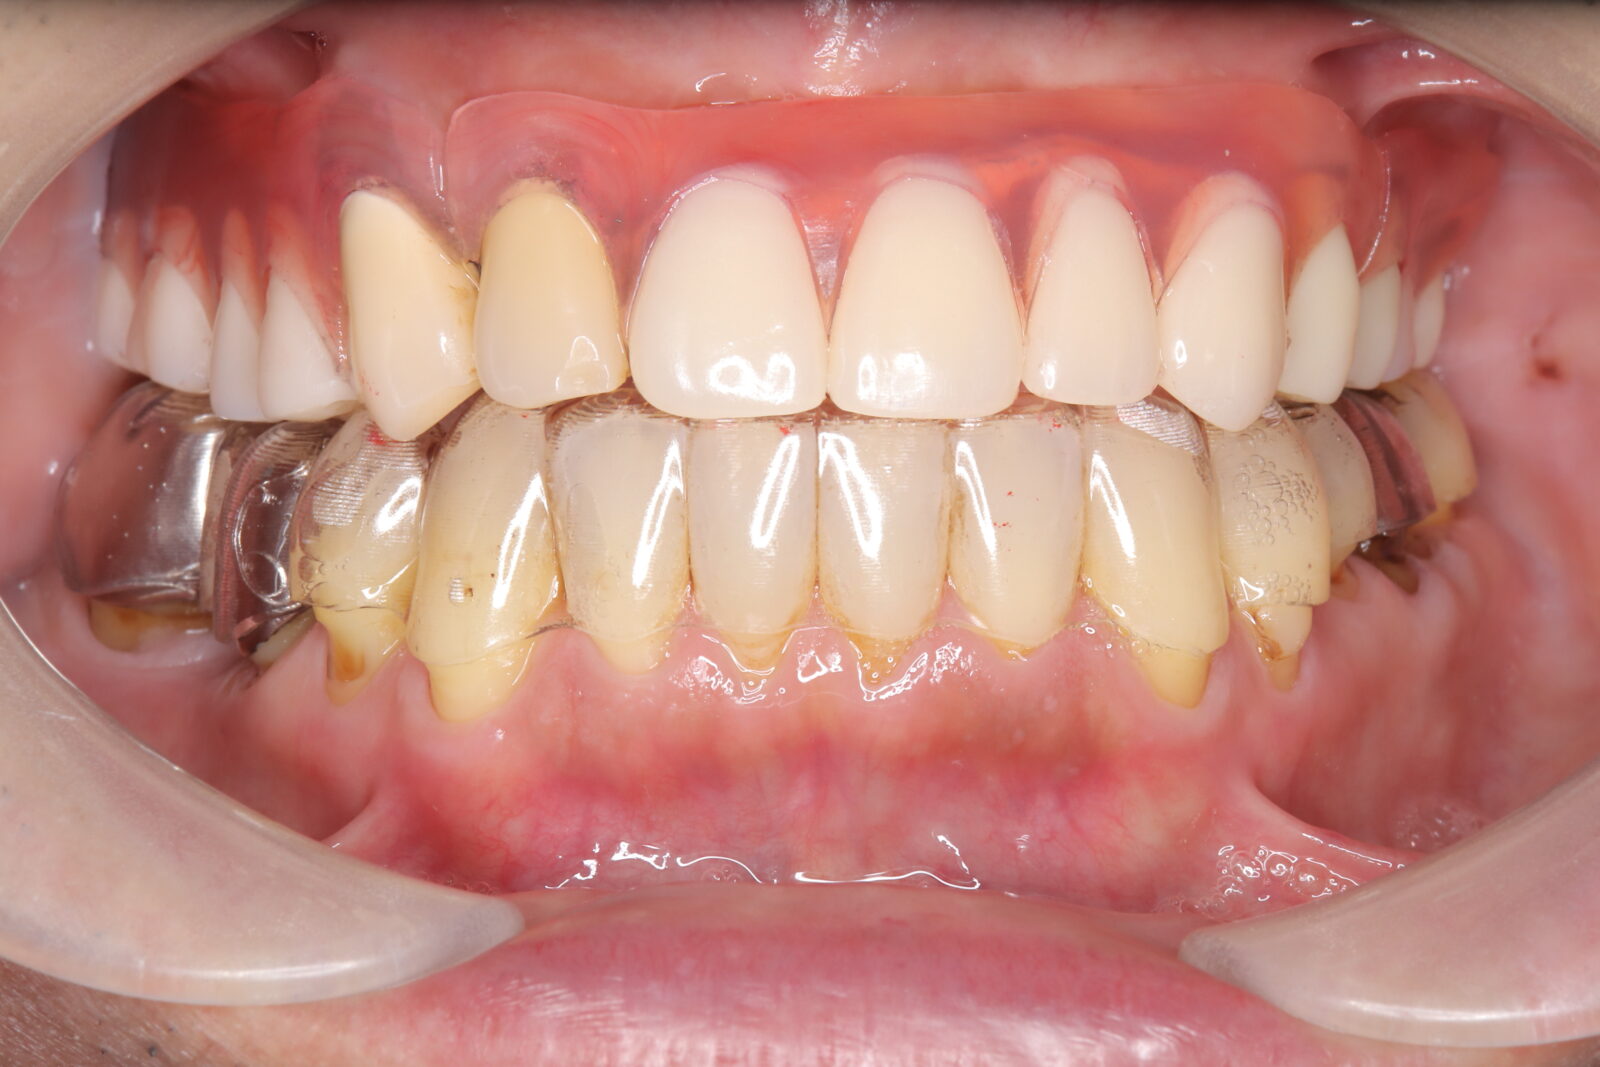

インビザライン(全体矯正)+ホワイトニングコース+セラミック治療の症例

過去にワイヤー矯正で治せなかったクロスバイト。インビザライン(全体矯正)とホワイトニングとセラミック治療で綺麗な笑顔へ。

・費用:726,000円(税込) ※ホームホワイトニングと右上6番ジルコニアクラウン含む

・治療期間:15ヶ月

・通院回数:10回

・32歳女性